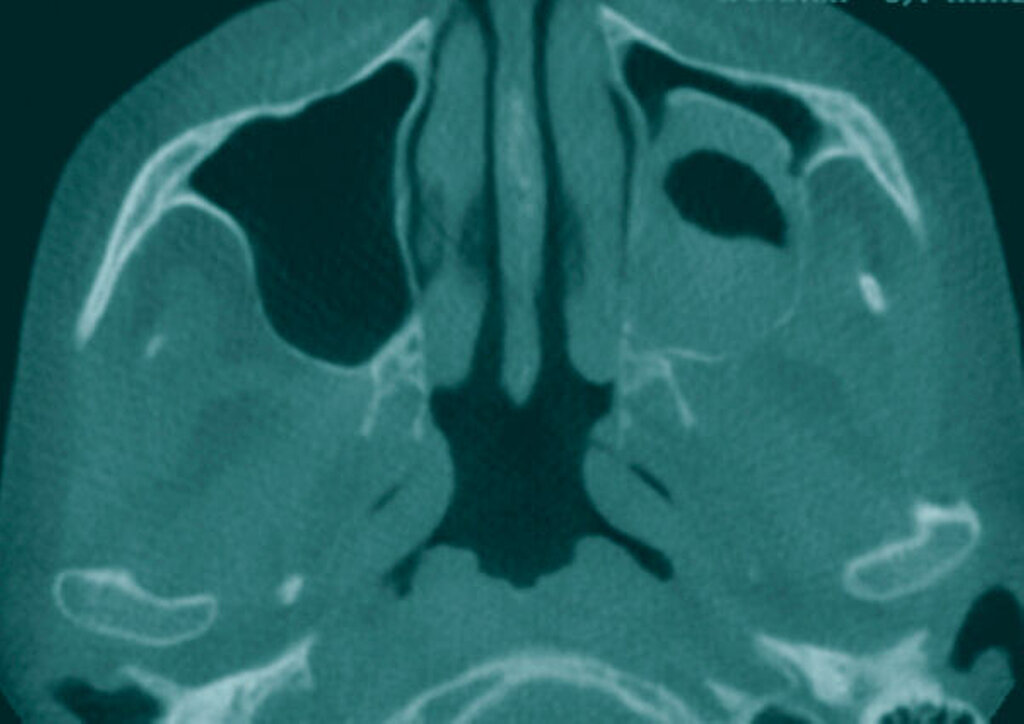

Die präoperativ durchgeführte Digitale Volumentomografie (DVT) zeigte eine zystische Raumforderung, die fast zwei Drittel der linken Kieferhöhle einnahm. Die Raumforderung hatte randständig eine weichgewebedichte Opazität mit zentraler Transluzenz und erschien fast „seifenblasenartig“. In regio 26/27 zeigte sich die bereits klinisch auffällige MAV. Radiologisch befand sich der Zahn 25 in direkter Nähe zum Befund. Das restliche Gebiss wies neben konservierenden und prothetischen Maßnahmen keine weiteren Auffälligkeiten auf (Abbildung 1).

Schmerzen und Sensibilitätsstörungen sind selten, weshalb diese Tumore aufgrund des langsamen Wachstums in seltenen Fällen auch groteske Ausmaße erreichen können. Typischerweise präsentieren sich Ameloblastome radiologisch als „seifenblasenartig“ oder „bienenwabenartig“ und weisen oft auch Wurzelresorptionen an benachbarten Zähnen auf [Castro et al., 2012]. Andere odontogene Tumore zeigen oft ähnliche radiologische Muster, weshalb differenzialdiagnostisch unter anderem auch immer an eine Keratozyste (ehemals keratozystisch odontogener Tumor [Thiem et al., 2019]) gedacht werden sollte [Römer et al., 2020].